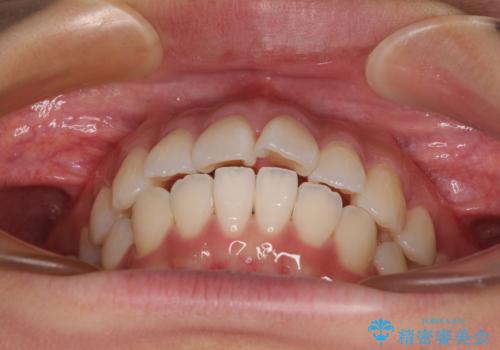

- 前歯が突出して、眠るときに口が開いてしまうことを気にして来院された患者様です。

横から見た際の口元の飛び出した印象も改善したいとのことで、上下左右の第一小臼歯4本を抜歯し、ワイヤー装置にて抜歯矯正を行うこととしました。